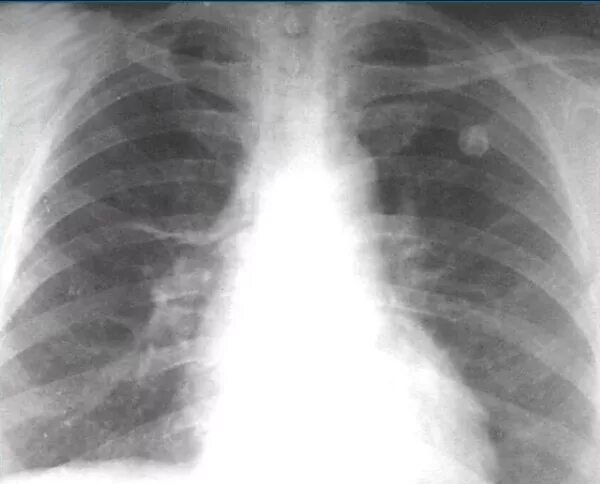

Очаг симон